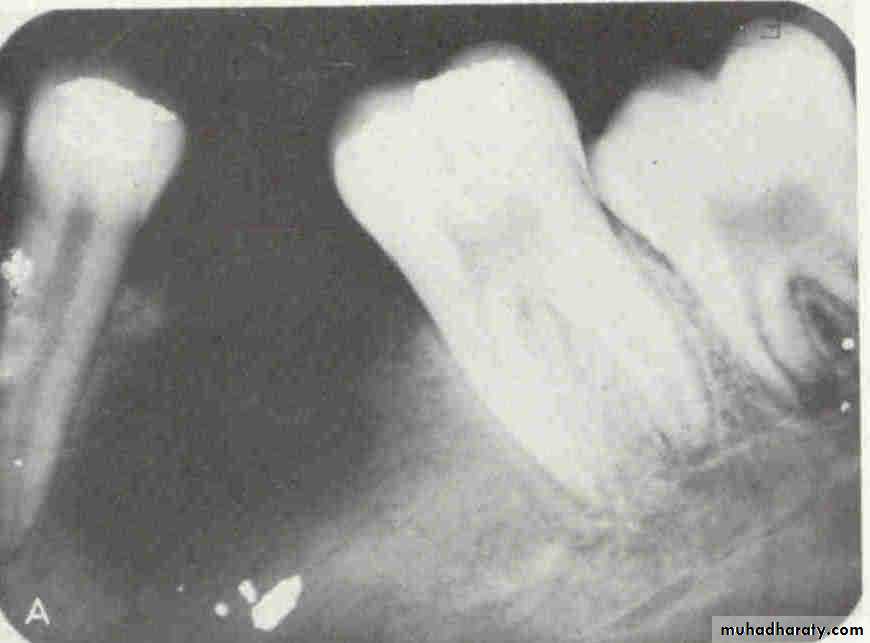

• 2.Position in the jaws:

• - Epicenter coronal to tooth- odontogenic epithelium.

• - Epicenter of the lesion is above the mandibular canal-odontogenic in origin .

• - Epicenter -below lDC- non odontogenic